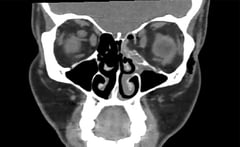

Investigatiile imagistice au aratat o fractura in cavitatea oculara stanga. Practic, un os al orbitei se rupsese, se arata intr-un raport publicat de jurnalul BMJ Case Reports, preluat de Live Science.

Desi astfel de fracturi sunt mai frecvente decat ne imaginam, in general sunt cauzate de traume – cand cineva este pocnit in ochi sau lovit de o minge, de exemplu, explica medicul Sam Myers, chirurg la Spitalul Universitar North Middlesex, din Londra, cel care a ingrijit-o pe femeie.

Accidentul pare sa fi aparut intr-un intreg context. Potrivit medicului, femeia era racita de cateva zile, iar in tot acest timp si-a tot suflat nasul. Iar felul in care a facut asta a fost crucial. Concret, de cate ori isi sufla nasul, femeia acoperea cate o nara, curatandu-le, astfel, pe rand. Procedand asa, presiunea la nivelul sinusurilor a fost dublata.

In plus, a mai mentionat medicul, pacienta fuma cate un pachet de tigari zilnic. Potrivit acestuia, fumatul schimba presiunea exercitata la nivelul sinusurilor, care sunt situate langa cavitatile oculare, marind predispozitia la astfel de fracturi.